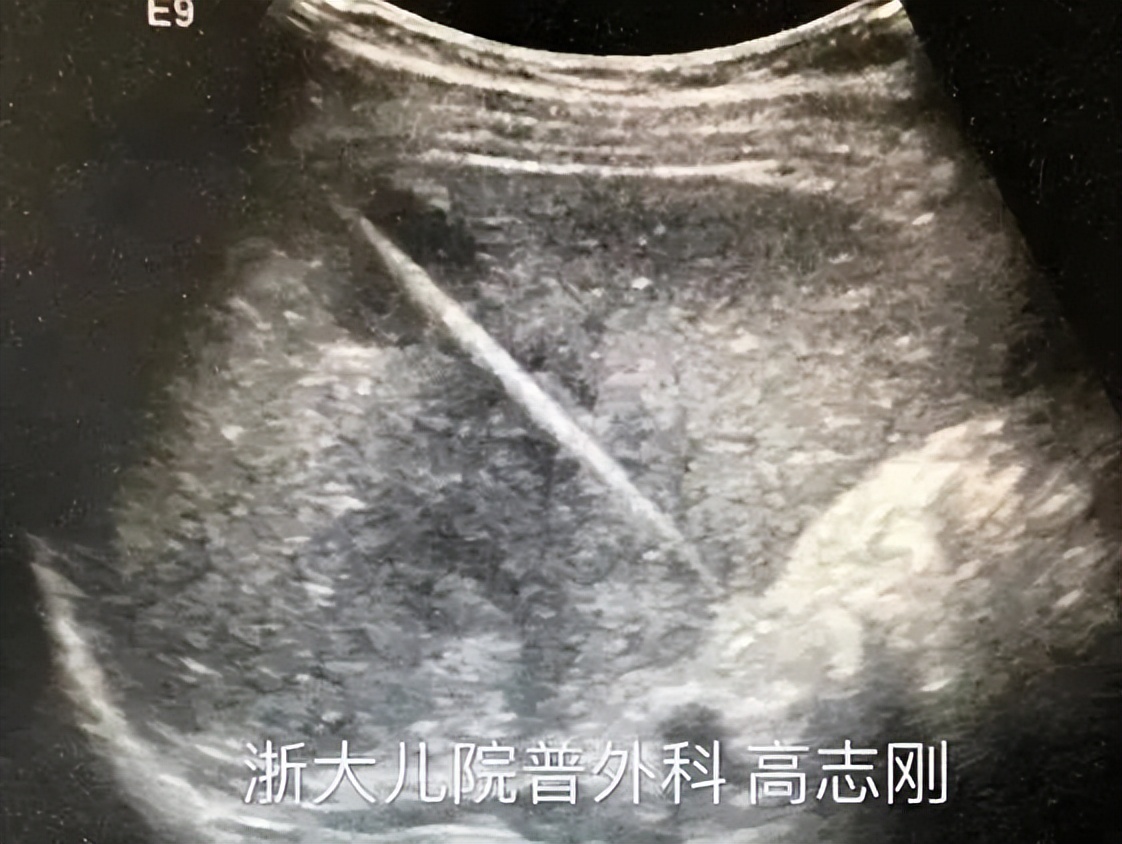

据这位妈妈回忆,当日,奶奶带着11个月大的孙女乐乐(化名)在阳台玩耍。就在转身的瞬间,奶奶隐约看到孙女把一个东西塞进了嘴里。看着阳台上散落的几枚装修时遗落的铁钉,奶奶心里急了:会不会把钉子吞进了肚子?奶奶赶紧把这事告诉了孩子爸妈。爸爸妈妈一听,不敢马虎,立即带着孩子到了当地医院。胸片显示,在乐乐的中腹部有一钉状致密影,长径约31.1mm,尖端位置朝上。

急诊科医生沈丹萍查看了宝宝的腹部平片报告,发现确有一枚长长的钉子,就在孩子腹部。

胃镜和胸片检查显示,乐乐体内的铁钉已经随着消化道进入了小肠,随着小肠的蠕动正往大肠方向移动。